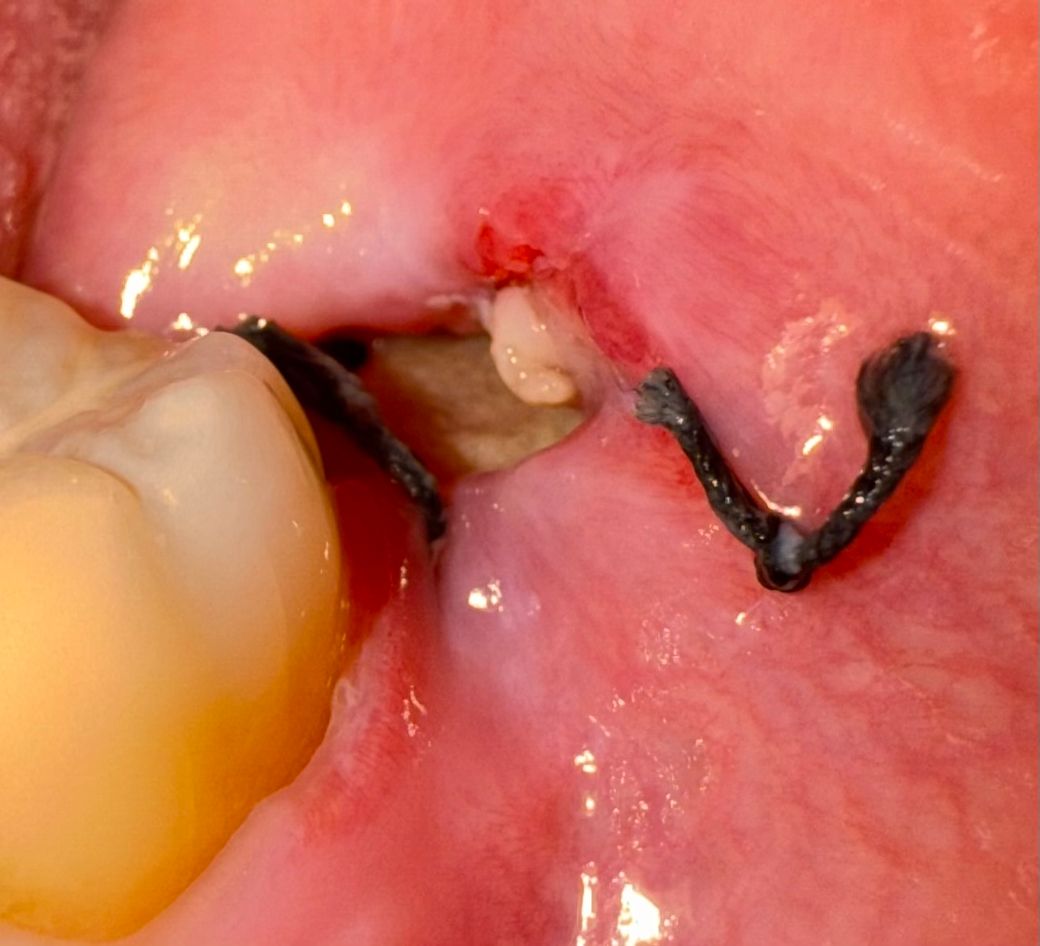

사랑니 뺀지 6일 됐고 밑에는 절개해서 꼬맸는데요.

위에는 잘 아물고 있는 것 같은데 밑에는 실밥도 끊어졌고 하얀색이 있어서 이수시개로 살살 빼보려고 했는데 안 빠지는데 이거 뭐예요..?.. 혹시 이거 구강 세척기로 하면 빠지는건가요? 통증이 조금 있고(참을만함) 진통제랑 항생제 복용하면서 핵사매딘으로 양치 할때마다 행궈주고 있어요. 드라이소켓인가요?

드라이 소켓은 아니고 잇몸치 치유되는 과정중에 생기는 자연스러운 현상이니 너무 걱정하지 않으셔도 될것같습니다.

잇몸 조직인 것으로 보입니다. 억지로 제거할 필요는 전혀 없으니 조심하고 닿지 않는 것이 좋습니다.

드라이소켓의 양상은 아니고요 치유과정에서 생기는 염증,육아조직 및 이물질 같습니다 해당 부위 가글 살살하면서 이물질은 빼주세요

하얀색 물질이 보이는 것은 혈병일 가능성이 높습니다. 드라이소켓은 아닌 것으로 보이며, 헥사메딘으로 지금처럼 관리하는 것이 세균 번식을 억제하고 상처 부위를 청결하게 유지하는 데 도움이 됩니다.

구강 세척기로도 세척을 해주는 것이 좋지만, 너무 강한 압력으로 세척하지 않도록 주의를 요합니다.